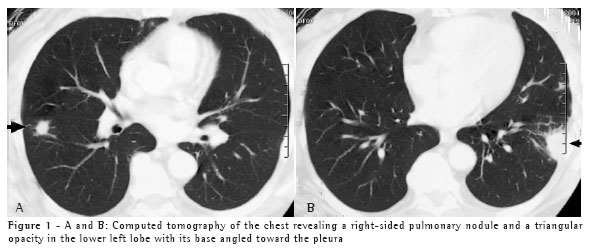

Case 2

A 50-year-old white male, resident of the city of Blumenau and a stonemason, presented a clinical profile similar and simultaneous to that described in Case 1 ten days after the cleaning of the same area, in which there was bat guano. The patient was exposed to a large quantity of dust in an enclosed space. The patient was hospitalized for seven days. Two chest X-rays, one presenting diffusely disseminated micronodules in both lungs and one showing the subsequent control of the condition, are shown in Figures 2A and 2B.

Epidemiological history can raise diagnostic suspicion. Knowledge of clinical syndromes, together with clinical suspicion, can avoid the use of empirical treatment. Radiological findings, negative test results, and the high frequency of tuberculosis in Brazil were the motivations for prescribing tuberculosis treatment for both patients. Immunodiffusion test results, although negative for these two patients, have high sensitivity and are positive in approximately 75% of cases.(6) Length of exposure determines disease severity. This explains the fact that the second patient, who was the one who swept the area, presented a more severe form of the disease, with diffuse pulmonary alterations on the chest X-ray, and required hospitalization. However, a short exposure time results in focal pulmonary lesions, as in Case 1.